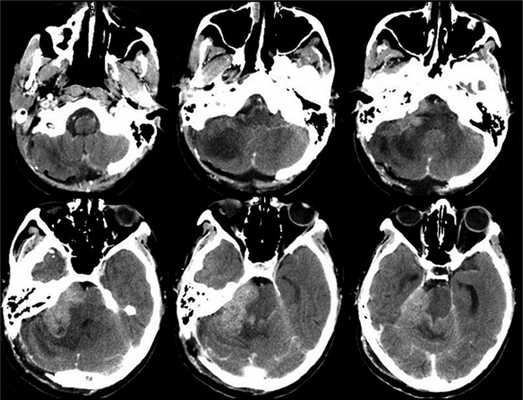

Рис. 3. Рис 3. КТ головного мозга, выполненная на 6-е сутки после операции. Признаки быстрого продолженного роста опухоли.